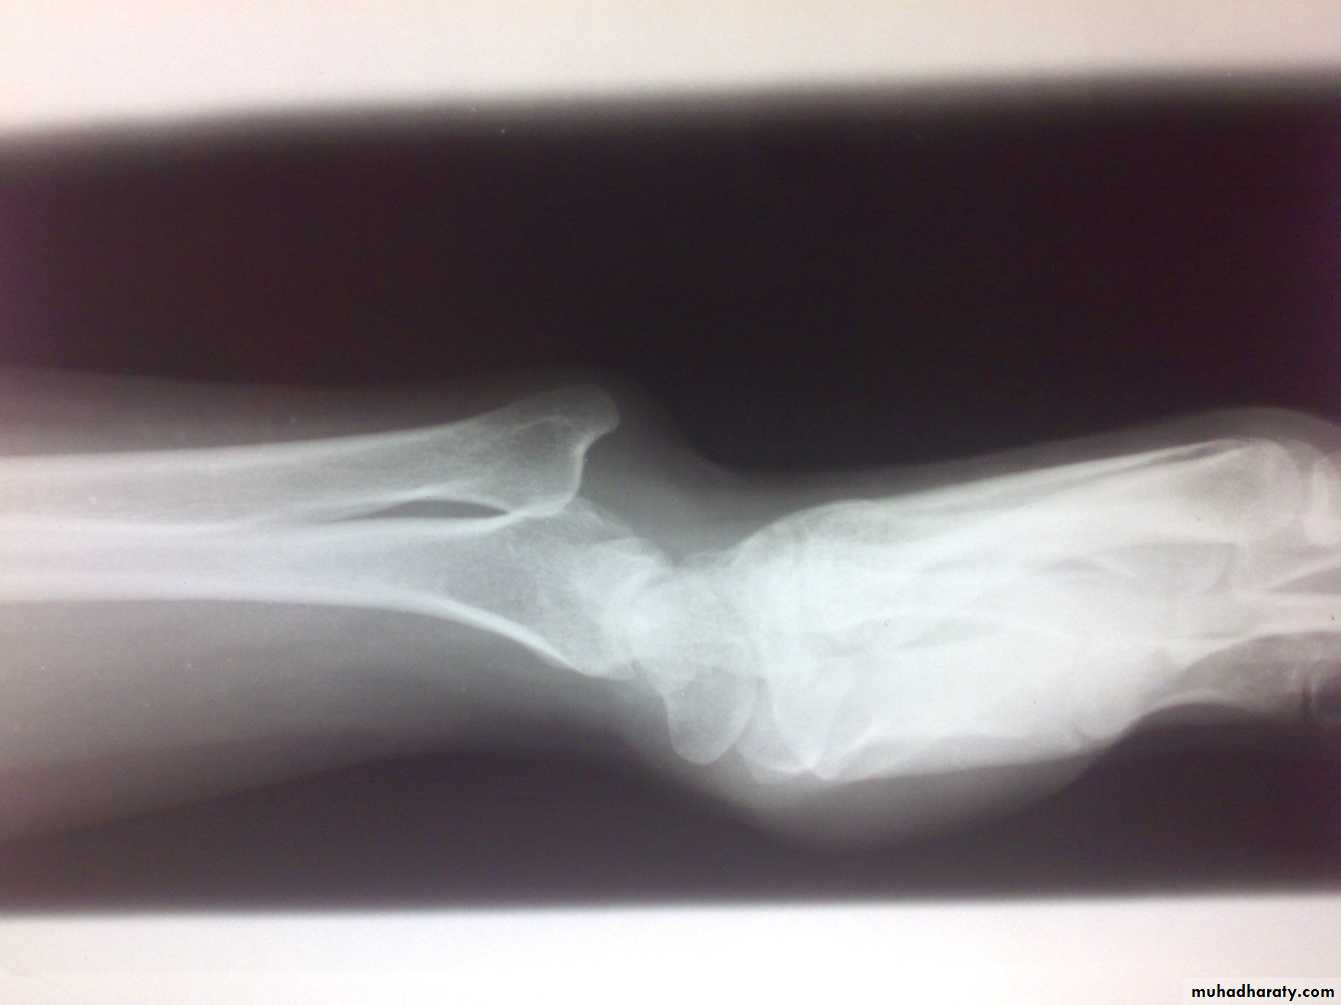

Instability of distal radioulnar joint

Post-traumatic; after fracture of lower radius (Galeazzi fracture dislocation).Associated with rheumatoid arthritis.

Painful restriction of pronation and supination.

Backward prominence of the lower ulna.

Piano key sign; balloting the lower ulna.